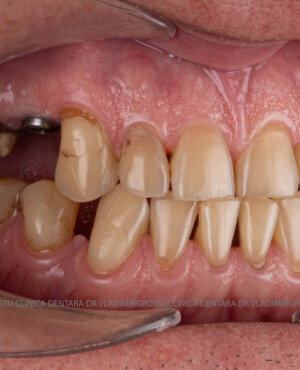

După inserarea unui implant dentar – o rădăcină artificială din titan sau zirconiu –, urmează etapa de protezare, adică atașarea unei structuri protetice (coroană, punte sau proteză) care înlocuiește dintele lipsă.

- Punte pe implanturi – pentru mai mulți dinți lipsă în aceeași zonă

- Punte fixă pe 2 sau mai multe implanturi

- Chirurgie implantologică ghidată, minim invazivă